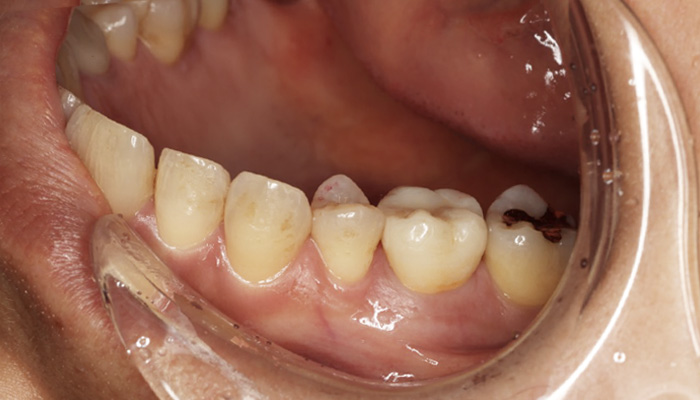

症例 14

治療前

治療後

| 主訴 | 歯の色が気になる。 |

| 先生からの提案 (治療内容について) |

全顎的に虫歯治療とジルコニアセラミックス補綴で色を均一化しました。 歯根破折していた歯が一本あったのでインプラントを行いました。 |

| 治療期間 | 1年 |

| 治療費 | 4,310,000円 |

| 治療のリスク | くいしばりが強い患者さんなので歯根破折が心配。 |